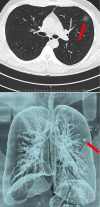

Effectiveness of Computed Tomography in the Diagnosis of Novel Coronavirus-2019

Coronaviruses (CoV) belong to the coronavirus genus of the coronaviridae family. All CoVs are pleomorphic RNA viruses containing crown-like peplomers of 80-160 nm in size. This virus is a zoonotic pathogen seen with a wide range of clinical features from asymptomatic state to intensive care in humans. So far, seven human coronaviruses have been identified with the last one being Coronavirus-2019 (COVID-19). These pathogens typically lead to mild disease, but SARS and MERS type coronaviruses have caused severe respiratory disease and even mortality within the last 20 years. COVID-19 virus has rapidly spread worldwide after China and is continuing to cause huge economical and social impacts. Given the scarcity of resources including healthcare staff, hospital capacities, test kits, etc., timely diagnosis and treatment of this virus are of paramount importance. However, there is no vaccination or drug developed for the treatment of this disease up to today. Because the spreading rate of the virus is very high worldwide and there is no definitive treatment, diagnosis becomes even more important. The objective of this review is to evaluate the use of chest computed tomography, one of the commonly used radiologic imaging modalities, in the diagnosis of COVID-19 in light with the current literatüre.